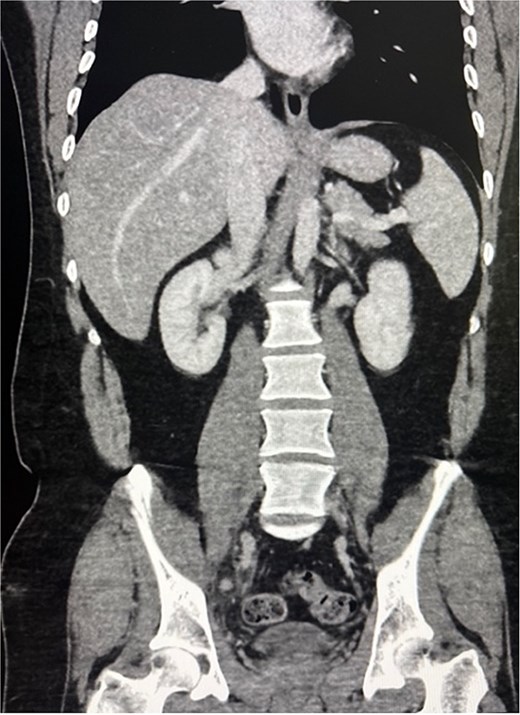

A 31-year-old male presented to the emergency department with a history of abdominal pain for 3 days. The pain was diffused around the umbilicus, subsequently migrated to the right lower quadrant and to the right groin, and was associated with nausea, vomiting, and anorexia. Abdominal exam revealed severe right lower quadrant and right groin tenderness with rebound tenderness. Laboratory findings showed leukocytosis with a white blood cell count of 17 × 109/L. Contrast-enhanced CT scan of the abdomen and pelvis revealed findings consistent with acute, uncomplicated appendicitis, including an appendix ~1 cm in diameter and periappendiceal fat stranding. The appendix was visualized to be within the pelvis (Fig. 1).

CT scan of the abdomen and pelvis showing acute appendicitis with the appendix extending toward the right femoral canal.